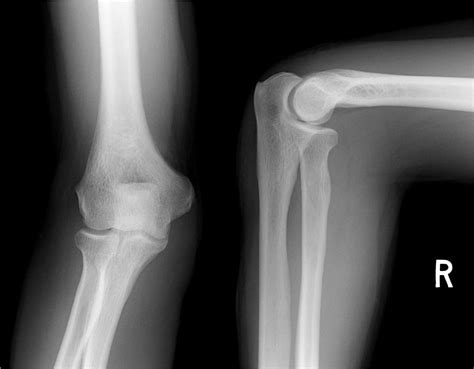

First up on our X-ray tour is the Anteroposterior (AP) view of the elbow. This is usually the first picture taken, and it gives us a nice, straight-on look at the elbow joint from the front. Imagine you’re looking directly at the palm of your hand – that’s essentially the direction the X-ray beam is traveling: from the front (anterior) through the elbow to the back (posterior). In this view, you’ll see the distal humerus, the proximal radius, and the proximal ulna. The key here is to observe the alignment. The trochlea of the humerus (the spool-shaped part that articulates with the ulna) should align nicely with the trochlear notch of the ulna. Similarly, the capitellum of the humerus (the round knob on the side) should articulate smoothly with the head of the radius. In a normal AP view, you’ll notice clear joint spaces between these bones, indicating healthy cartilage. There shouldn’t be any overlapping of bony structures that suggests displacement, and the overall contour of the bones should be smooth. We’re looking for well-defined edges and no signs of lucency (dark areas) or opacity (bright areas) that aren’t normally present, which could indicate fractures or bone spurs. The olecranon process, that prominent bump at the back of the elbow, will be clearly visible. Pay attention to the relationship between the radial head and the capitellum – they should fit together snugly. If you see any widening of the joint space or misalignment, it might suggest a problem like a ligament injury or dislocation, but in a normal AP view, everything sits just right. This view is fantastic for assessing the overall width of the joint and for spotting fractures in the distal humerus or proximal ulna/radius that might be missed on other views. It’s the baseline, guys, the first step in confirming that everything is structurally sound in your elbow.

Next, we move on to the Lateral view of the elbow. This view is absolutely critical because it gives us a profile, a side-on perspective, of the elbow joint. The X-ray beam here travels from the side of the elbow, typically through the pinky-finger side, to the thumb-finger side. This angle is super important for visualizing specific structures and their relationships that the AP view can’t show as clearly. When you look at a normal lateral elbow X-ray, you’ll see the humerus sitting above the ulna and radius. The most telling sign of a normal lateral view is the ‘fat pad’ sign . There are usually small, radiolucent (dark) areas within the joint capsule, representing fat. In a normal elbow, the anterior fat pad is often obscured or very faintly seen, lying along the anterior aspect of the distal humerus. The posterior fat pad, however, normally sits in its groove on the posterior aspect of the humerus and is usually not visible on a standard lateral X-ray. If the posterior fat pad is visible, it often means there’s fluid within the joint, which could be due to a fracture (like a radial head fracture) or other trauma, pushing the fat pad out of its normal position. So, a normal lateral view is one where the posterior fat pad is not seen. Another key landmark is the ‘coronoid line’ . Imagine drawing a line along the anterior border of the coronoid process of the ulna; this line should intersect the capitellum of the humerus in a normal, reduced elbow. Significant displacement or abnormal angulation here can indicate a fracture or dislocation. The olecranon process will also be prominent, and you can assess its relationship with the olecranon fossa of the humerus. The radial head should be clearly visualized articulating with the capitellum. The lateral view is your best friend for spotting elbow dislocations and subtle fractures, especially those involving the radial head or olecranon, because it shows the anterior-posterior relationship of the bones so well. It’s essential for evaluating joint congruity and detecting any subtle swelling or effusion within the joint. Remember, a normal lateral view is clean, showing good alignment and no displaced fat pads.